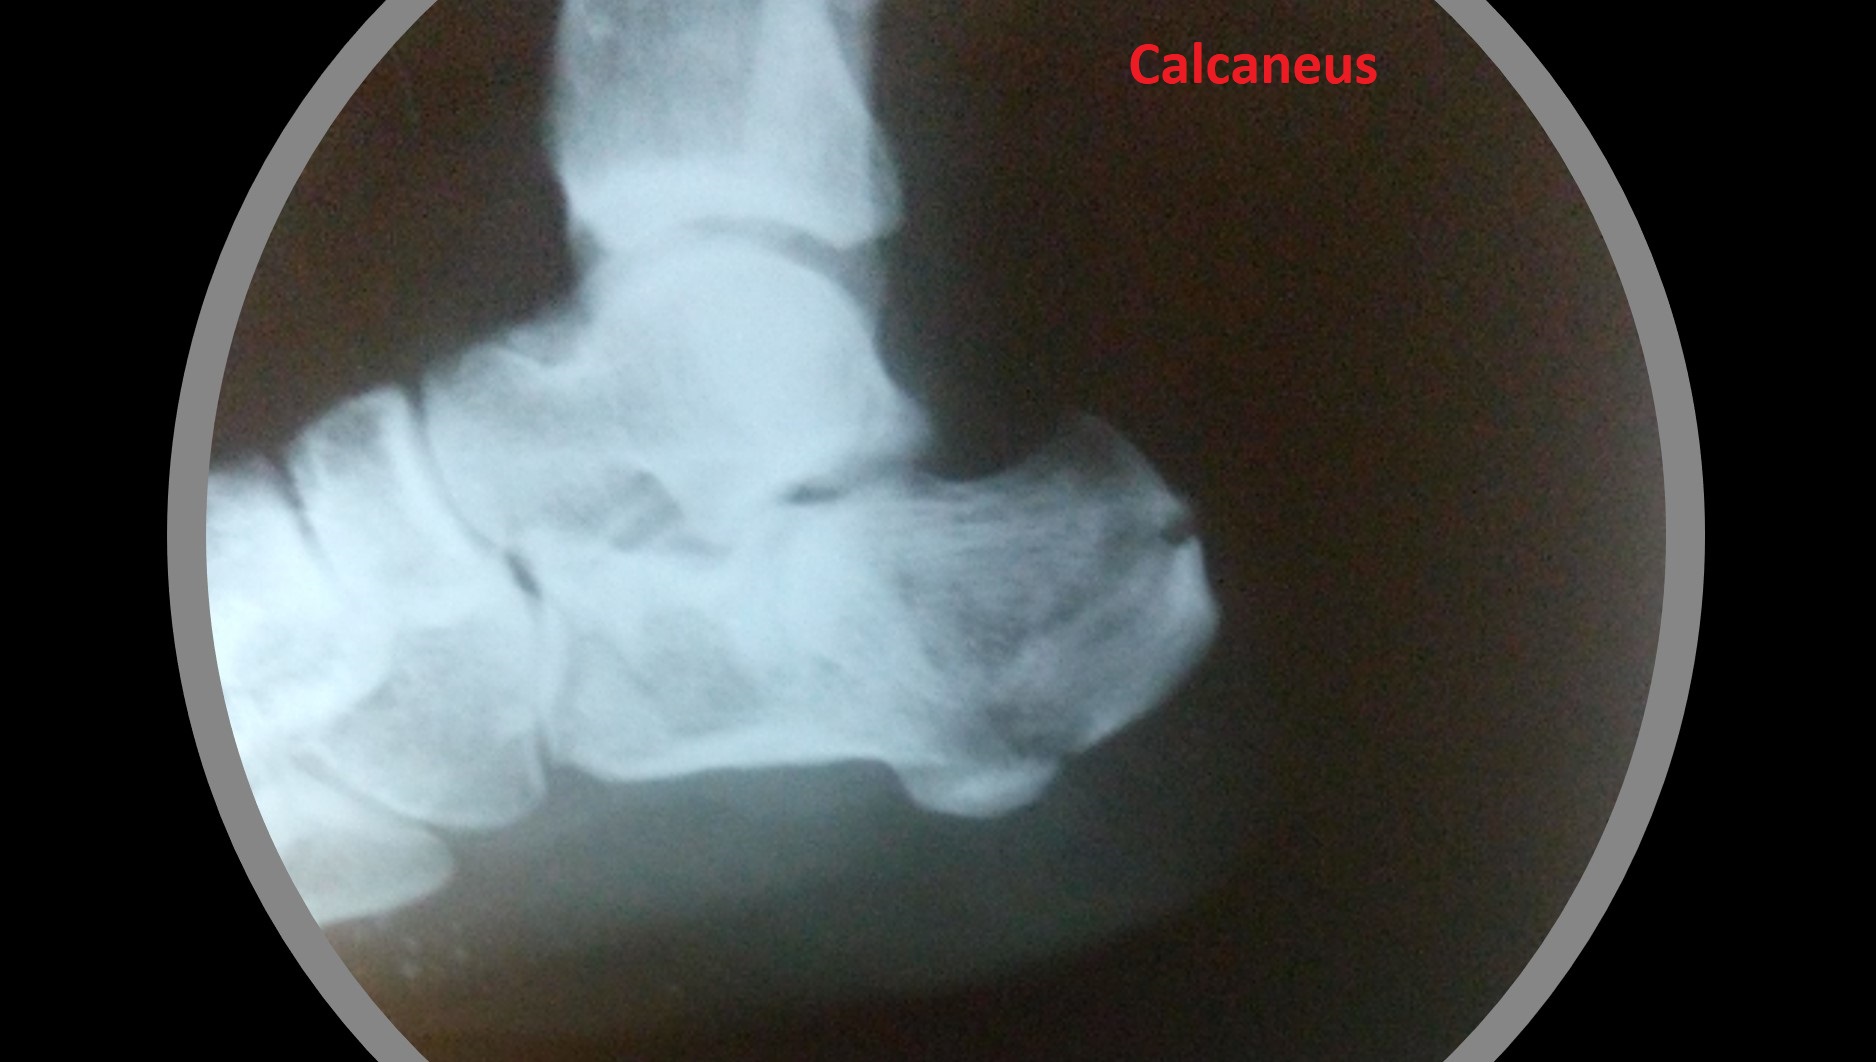

• It can be applied to any intraarticular fractures, distal end radius, elbow, ankle and foot.